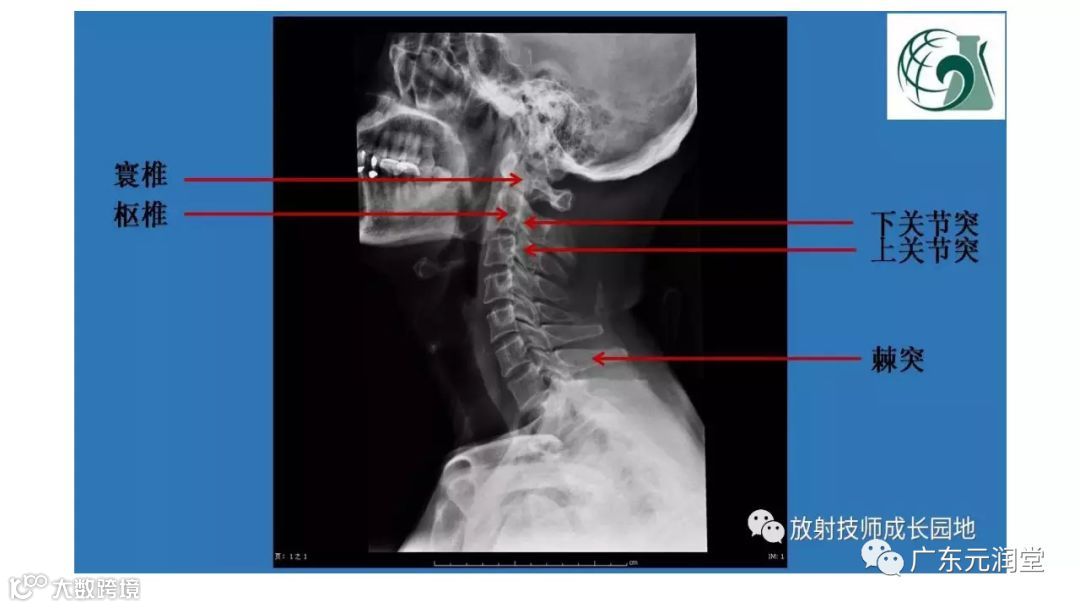

颅底孔道解剖详解

值得收藏!